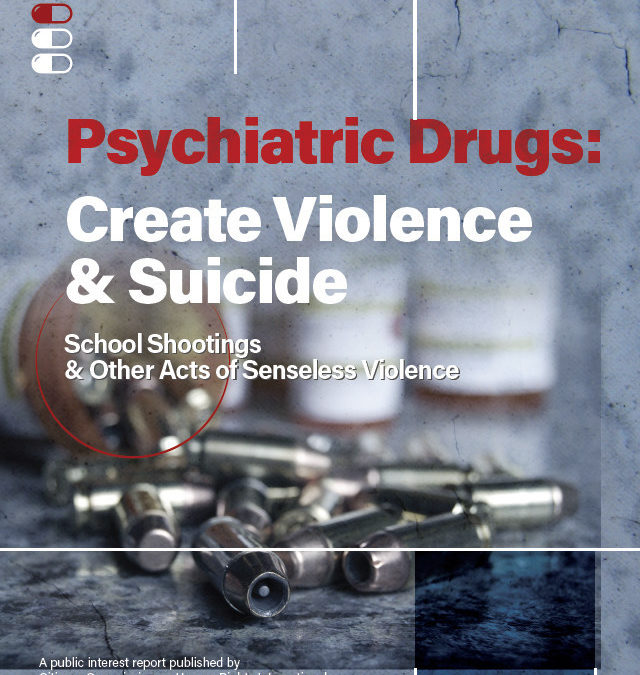

Another Psychiatric Drug, Another Act of Senseless Violence: the All-Too Often Finding in Mass Killings CCHR reports

Montgomery County Coroner has confirmed that the alleged Dayton, Ohio shooter had the benzodiazepine, alprazolam, in his system along with cocaine, alcohol and other substances.[i] In its report, Psychiatric Drugs...

A Warning that cannot be ignored: Psychiatric Drugs Create Violence CCHR calls for Urgent Government Investigation

The spate of recent mass shootings has prompted the mental health watchdog, Citizens Commission on Human Rights International (CCHR) to reiterate the urgent need for State and a Federal government investigation into...

Getting it Right About Antidepressants, CCHR and a Global Concern About Psychiatric Drug Dependency and Risks

Current debates in the media about antidepressants raise important issues—global antidepressant use is soaring, but the once-touted “miracle pills” now carry international drug regulatory agency warnings that...

CCHR Exhibit Warns Lawmakers that Psychotropic Drugs May Contribute to Violence and Suicide

The Citizens Commission on Human Rights (CCHR), a mental health watchdog dedicated to the protection of children, unveiled a new exhibit in Tallahassee designed to educate lawmakers on the dangerous side effects of...